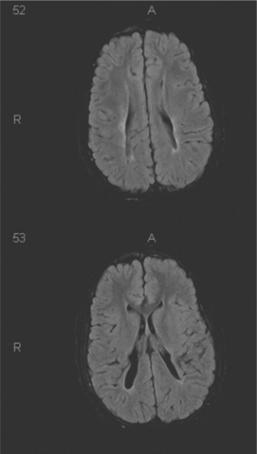

Periventricular lesions can be either cystic, as in periventricular leukomalacia (PVL), or more diffuse and result in abnormal myelination (Fig. 35-2). Diffuse periventricular myelination abnormalities can be found in up to 65% of premature infants when they reach full-term (9 months from conception). The incidence of PVL has declined somewhat, and PVL is seen in only 5% of this population. During the preterm period infants are at heightened risk for ischemia in the periventricular areas. The heightened risk is the result of passive-pressure circulation in the premature infant. The autoregulation of CNS blood flow normally present in full-term infants is absent, and the CNS blood pressure is more dependent on peripheral pressure. The premature infant between 23 and 32 weeks’ gestation is at the highest risk of periventricular injury. As the periventricular white matter begins to myelinate, the risk of hypoxic injury declines.

Figure 35-2 Magnetic resonance image of a periventricular leukomalacia with cystic formation extending into the parenchyma in a child with quadriplegic cerebral palsy. Top and bottom are serial sections in the same brain. In this child, the ventricles are a normal size. The abnormal finding is in the bottom slice where the cystic changes (black) extend into the brain tissue. (Courtesy Allan Glanzman, Children’s Seashore House of the Children’s Hospital of Philadelphia, PA.)